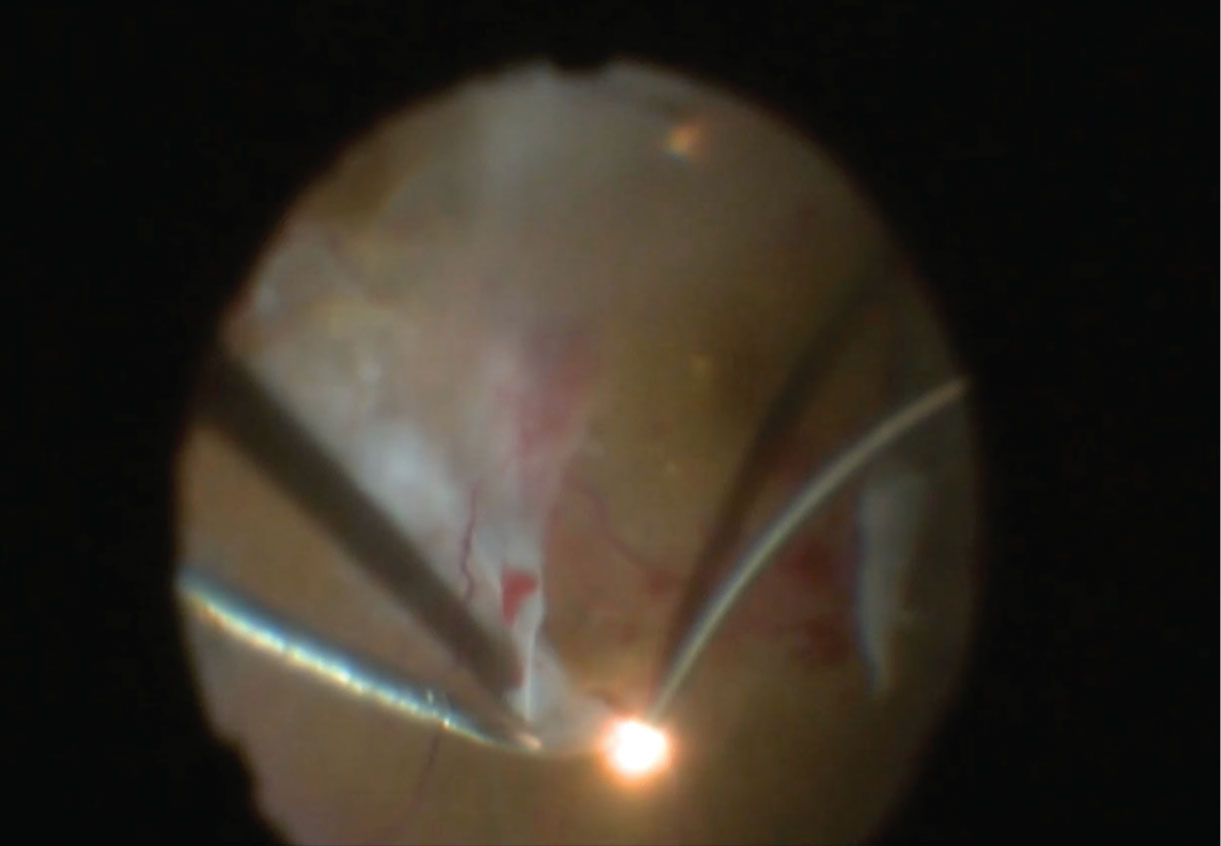

![]() |

| Figure 2. In laser-light-assisted retinal membrane delamination, the blunt curved end makes a perfect fit along the retinal surface and provides good visibility of the tissue plane. |

Retinal membrane delamination is the process of separating adhesions between membranes and the retina.

In our experience, the lighted curved laser probe has two properties that make it ideal for membrane delamination (Figure 2). First, its curvature, similar to the viscodissection cannula, as Jorge Fortun, MD, and Baker Hubbard 3rd, MD, reported,3 allows the orientation of the probe to be parallel with the retinal surface.

This results in less traumatic blunt dissection when pulling on membranes with forceps. Secondly, the light source allows for direct visualization of the membrane and retinal interface and may allow the surgeon to perform bimanual membrane manipulation without a chandelier.

Despite the usefulness of the lighted curved laser probe, it’s important to note that when working so close to the retinal surface the lighting will be very intense in the immediate area, while visualization and illumination of the adjacent structures may be less clear. Be cautious when using the probe to perform blunt dissection to membranes very tightly attached to the retinal surface; this can lead to iatrogenic tears.4

The fact that the illuminated laser probe is often opened and paid for anyway in diabetic vitrectomy cases for the endoretinal laser portion of the surgery is another reason why it’s one of our frugal faves.